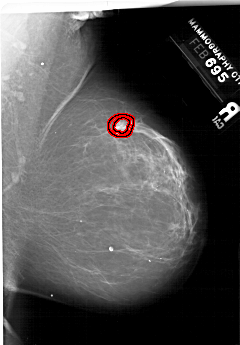

A_1999_1.RIGHT_MLO

RIGHT_MLO LINES 6196 PIXELS_PER_LINE 4306 BITS_PER_PIXEL 12 RESOLUTION 43.5 OVERLAY

FILE: A_1999_1.RIGHT_MLO.OVERLAY

TOTAL_ABNORMALITIES 1

ABNORMALITY 1

LESION_TYPE MASS SHAPE IRREGULAR MARGINS SPICULATED

ASSESSMENT 5

SUBTLETY 3

PATHOLOGY MALIGNANT

TOTAL_OUTLINES 2